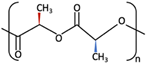

| 1 | PGA |  [39] [39] | High [29] | High [59] | − [59] | 4–12 months [60] | Tissue engineering. Drug-delivery systems [61] | |

| PLA | PLLA |  [62] [62] | High [63] | High [64] | − [51] | > 3.5 years [65] | Tissue engineering. Drug-delivery systems. Fixation devices [66] | |

| PDLA |  [62] [62] | High [63] | High [64] | − [64] | Longer than PLLA [34] | Tissue engineering. Drug-delivery systems, [66] | ||

| PDLLA |  [62] [62] | Lower than PLLA [37] | High [64] | − [64] | 12–30 months [37] | Tissue engineering. Drug-delivery systems [66] | ||

| 2 | PLLA/PGA |  [67] [67] | High [37] | High [68] | − [50] | 12–18 months [44] | Tissue engineering. Drug-delivery systems. Fixation devices [66] | |

| 3 | u-HA/PDLLA | Ca10(PO4)6(OH)2 +  | Low [54] | High [55] | + [56] | 12–18 months [69] | Tissue engineering. Fixation devices [70] | |

| u-HA/PLLA | Ca10(PO4)6(OH)2 +  | Higher than PLLA [19] | High [19] | + [19] | > 5 years [49] | Tissue engineering. Fixation devices [70] | ||

| 4 | u-HA/PLLA/PGA | Ca10(PO4)6(OH)2 +  | Similar to u-HA/PLLA [71] | High [72] | + [71] | 2–3 years [73] | Tissue engineering. Fixation devices [73] | |